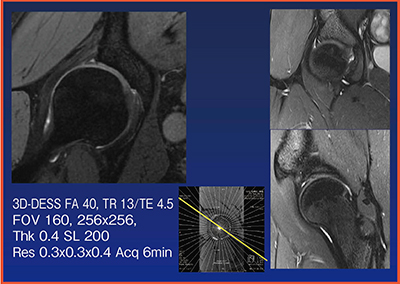

両側股関節の観察では大腿骨頭壊死を見逃さないことが特に重要となるが,通常のT2強調画像では骨髄の脂肪と骨髄浮腫がともに高信号となり判別できない。そのため,両側股関節では,T1強調画像と脂肪抑制T2強調画像を撮像すべきである。

また,股関節唇の撮像では,損傷の位置や角度を認識しやすくするために高分解能撮像を行い,放射状断面の再構成画像を提供している(図6)。

図6 股関節の放射状断面